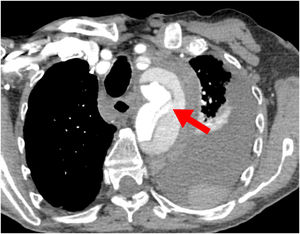

Probablemente la única situación en la que sea imprescindible para salvar la vida del paciente es cuando la falsa luz esté rota a nivel del arco, situación poco frecuente (figs. 1 y 2). Más frecuente es la presencia de malperfusión cerebral estática (por disección de uno o varios de los troncos supraaórticos, con oclusión de la luz verdadera) o de malperfusión visceral dinámica (por colapso de la luz verdadera, generalmente por reentradas en el arco o en la aorta descendente proximal). En estas dos circunstancias, aunque no es mandatorio, la sustitución del arco aórtico sí es la manera más eficaz de corregir la malperfusión20 (figs. 3 y 4).